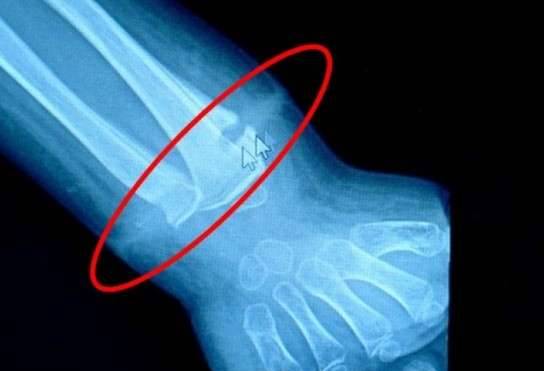

▼爷爷帮龙龙将手镯摘下来后,发现他的手腕上有一道很深的环状印痕,摸起来还有点硬。他们带龙龙去医院检查,医生说这是发炎,于是拿了消炎药给他吃,但情况没有好转。半个月过去,龙龙的左手开始红肿,情况越来越严重。

▼这根橡皮筋很细,一岁之后的孩子根本无法戴上去,很可能是龙龙出生后不久套在手腕上的。橡皮筋将一部份皮肤勒破,陷入皮下,后来皮肤长好,家人也就没有发现。

▼如果这次没有将橡皮筋取出来,任由它继续留在那里,龙龙以后可能需要截肢。